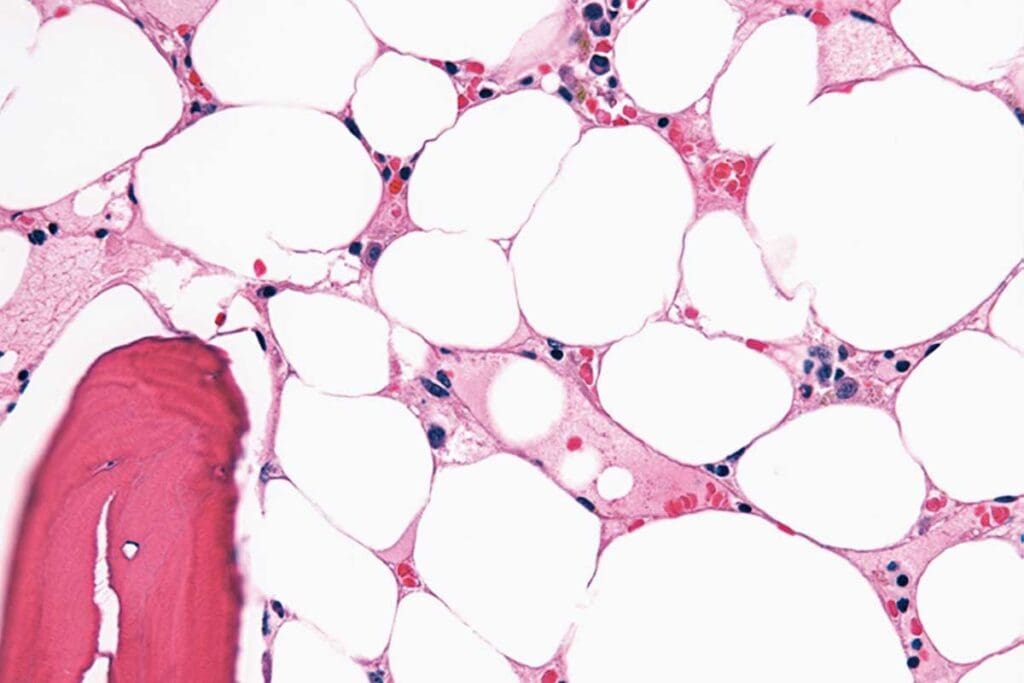

Diagnosing aplastic anemia involves clinical checks, lab tests, and bone marrow exams. Blood tests show low counts of all blood cells.

A bone marrow biopsy is ktofor diagnosis. It shows a marrow with fewer cells and more fat. The severity of the condition is based on these findings.